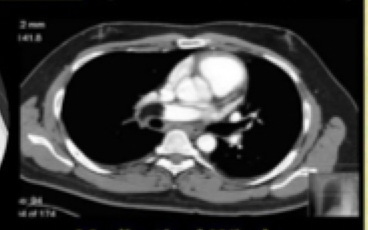

11

what type of window

Bone